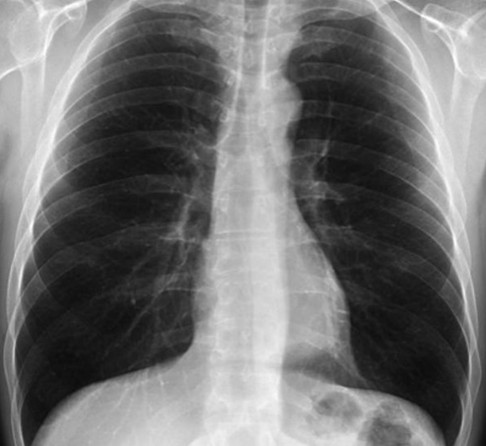

Pulmó sa.

Font: efesalud